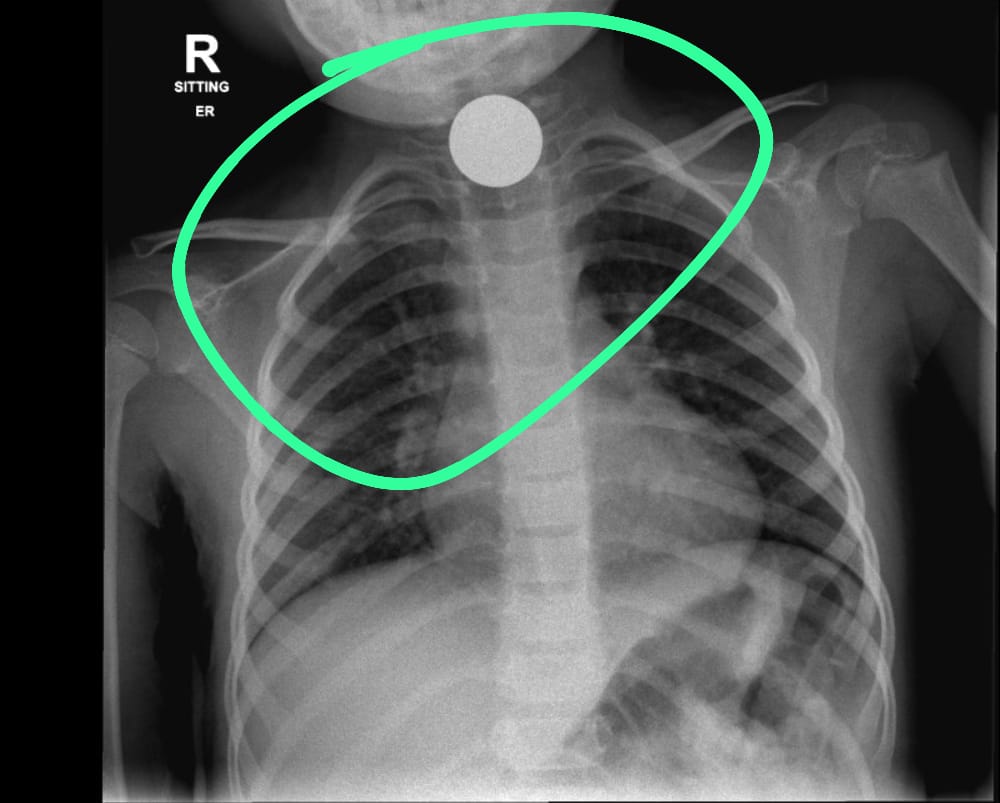

במקרה אחר, הובאה ילדה בת 4 אל בית החולים ובצילום רנטגן נמצאו בוושט של הילדה מטבעות כסף שגרמו לדחיקה של קנה הנשימה , דבר שמנע מהילדה לנשום כראוי.